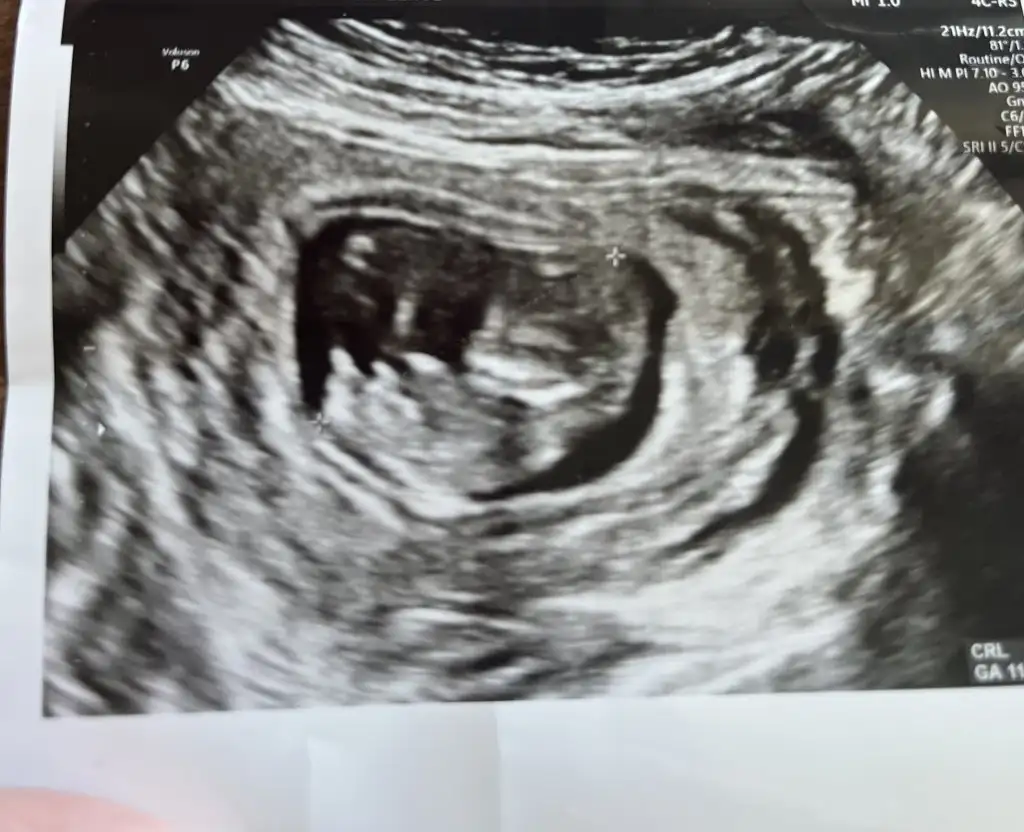

Evet burda gerçekten tam bir prensesDoktor kız dedii![]()

prenses gibi9+3 karından bakabilir misiniz?